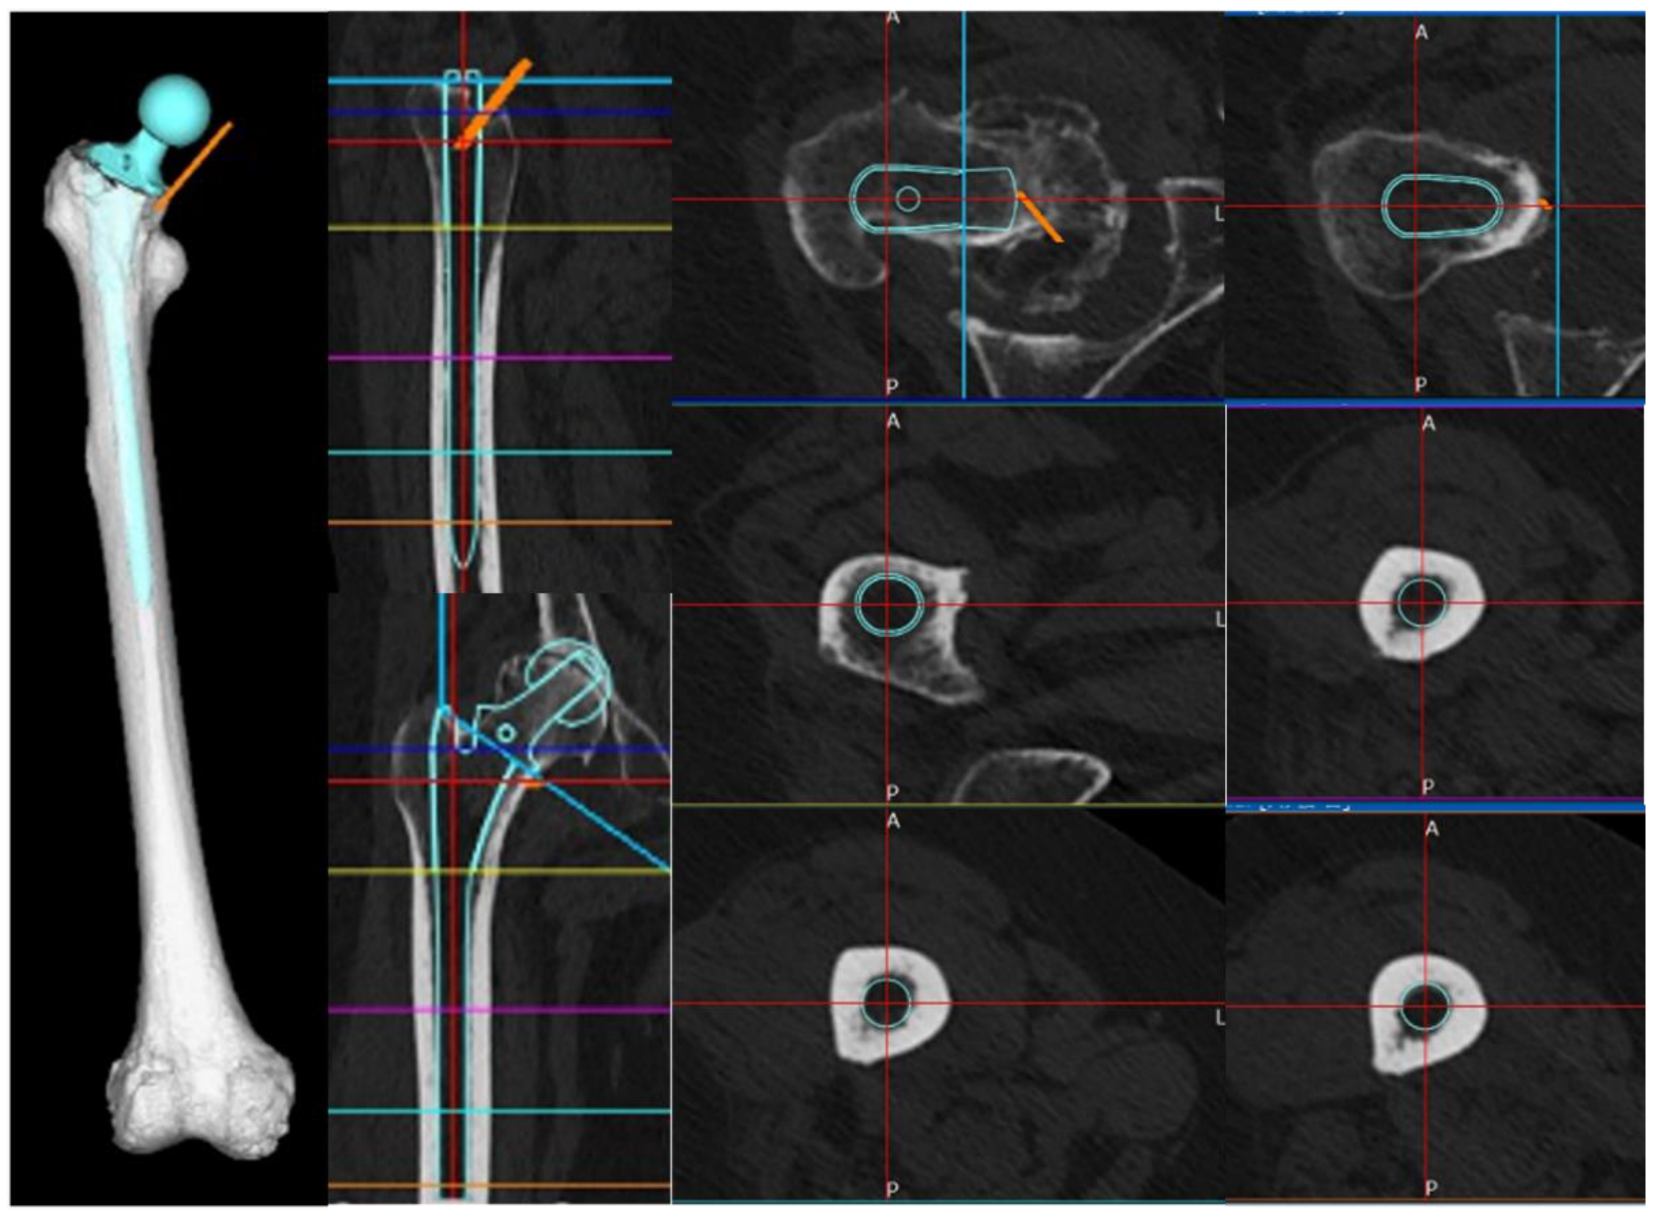

First, based on CT images, we simulated stem insertion using the ZedHip 3D preoperative planning software (Lexi Co., Ltd, Tokyo, Japan). The patient in this case had a narrow medullary canal and mild anterior bowing of the femoral shaft. As the selection of stems that could span the area of cortical hypertrophy and fit the femoral morphology of the patient was limited, we opted for the Arcos® One-piece Femoral Revision System (Zimmer, Warsaw, Indiana, USA) with a 9.5 mm diameter and 175 mm length, in the high offset configuration.

By registering the acquired stem STL data with a 3D model of the right femur in MF, we were able to replicate femur post-stem insertion. The insertion depth and alignment of the stem were reproduced in MF based on the simulation conducted in ZedHip, ensuring consistency in 3D coordinates across the analysis of each stem (Figure 4).

Figure 2. Plain radiograph and computed tomography (CT) images of the right femur. (a) Plain radiograph showing localized cortical hypertrophy at the subtrochanteric region. (b) Plain CT image showing no obvious radiolucent lines. (c) A full-length plain radiograph of the lower limbs showing no significant femoral bowing deformity.

Figure 4. Stem insertion depth and alignment. Preoperative planning was performed using three-dimensional (3D) ZedHip software. The stem was planned to be inserted at a 32° anteversion angle relative to the condylar axis on the femoral horizontal section, a 3° valgus angle relative to the femoral axis on the femoral coronal section, a 5° flexion angle relative to the femoral axis on the femoral sagittal section, and a depth of 11 mm from the apex of the greater trochanter.